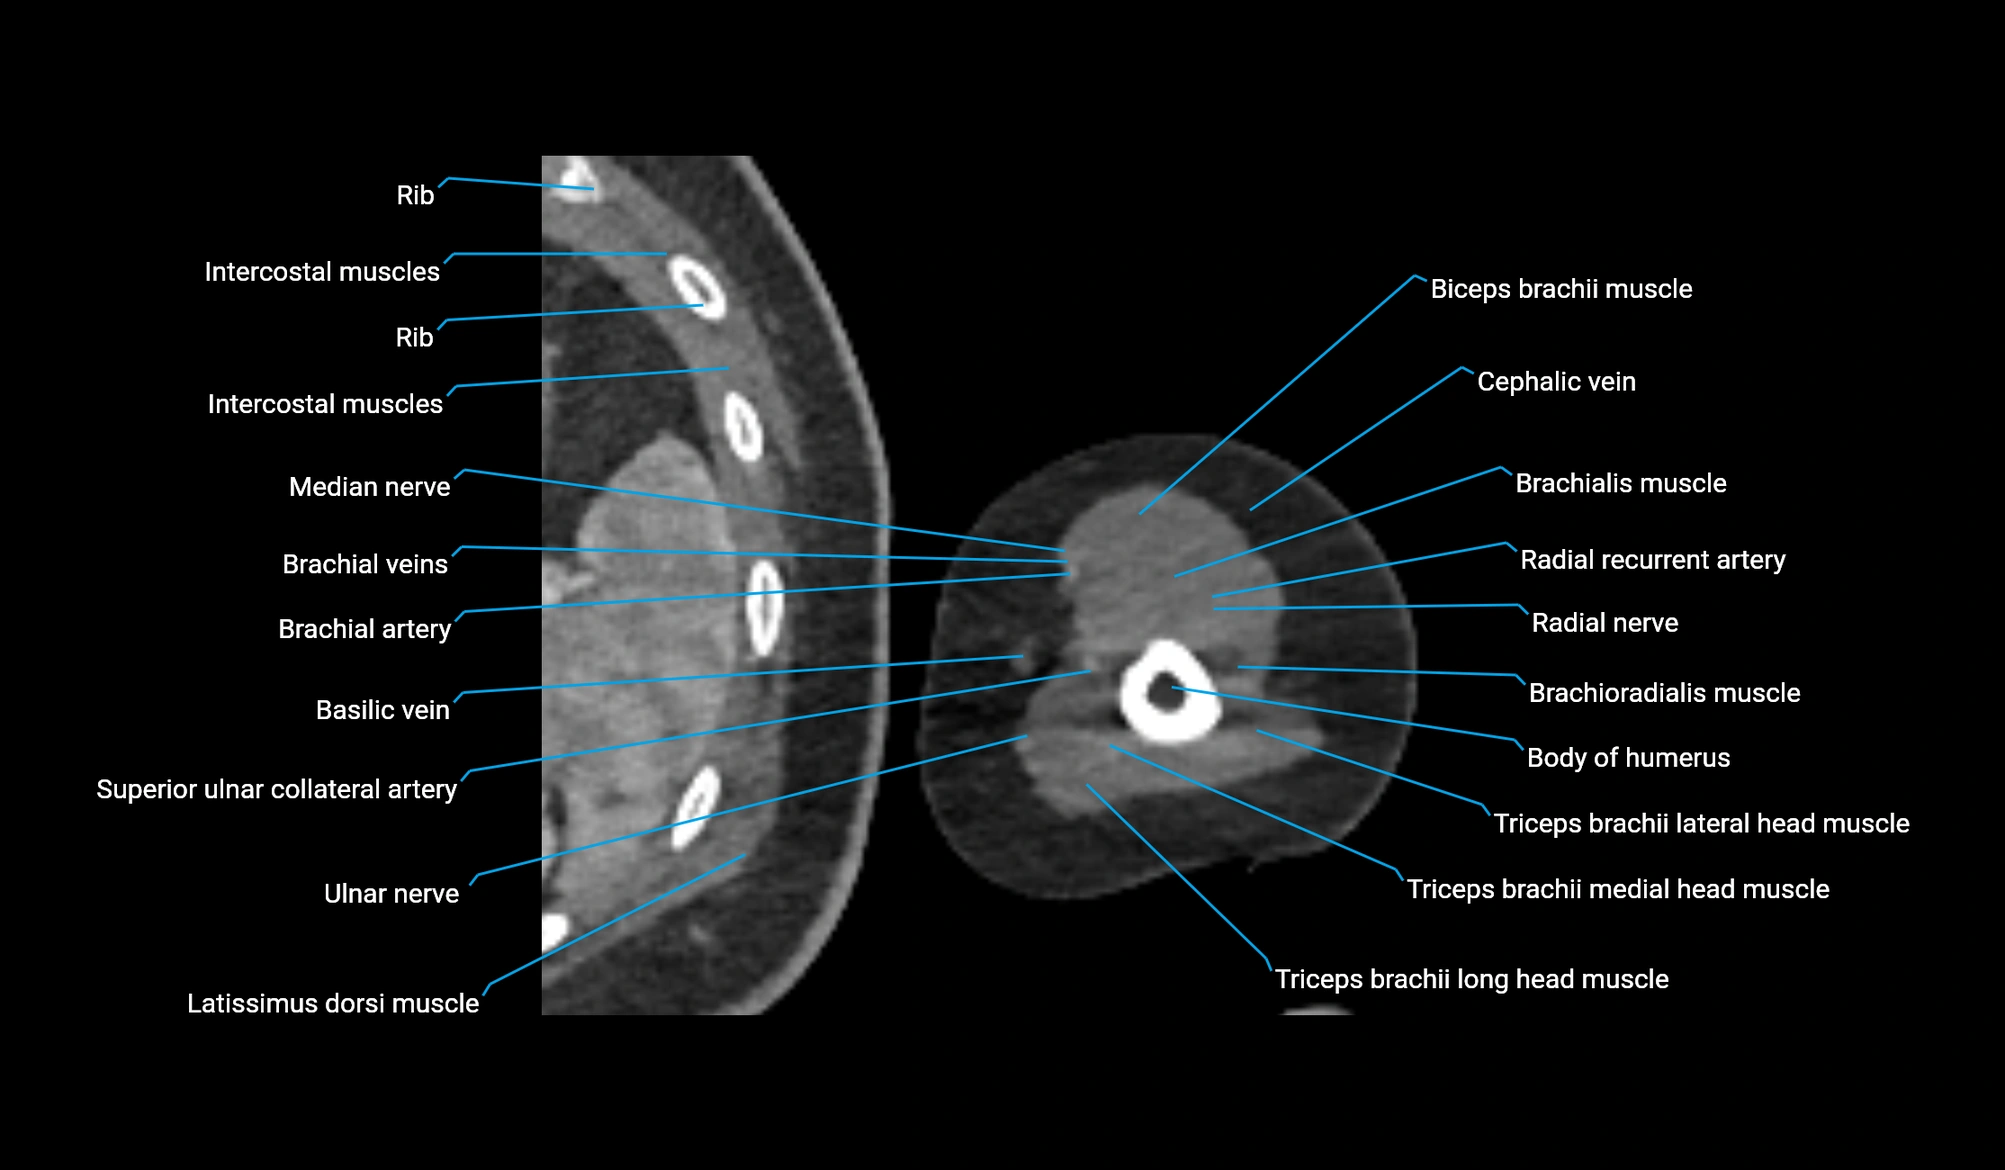

CT image